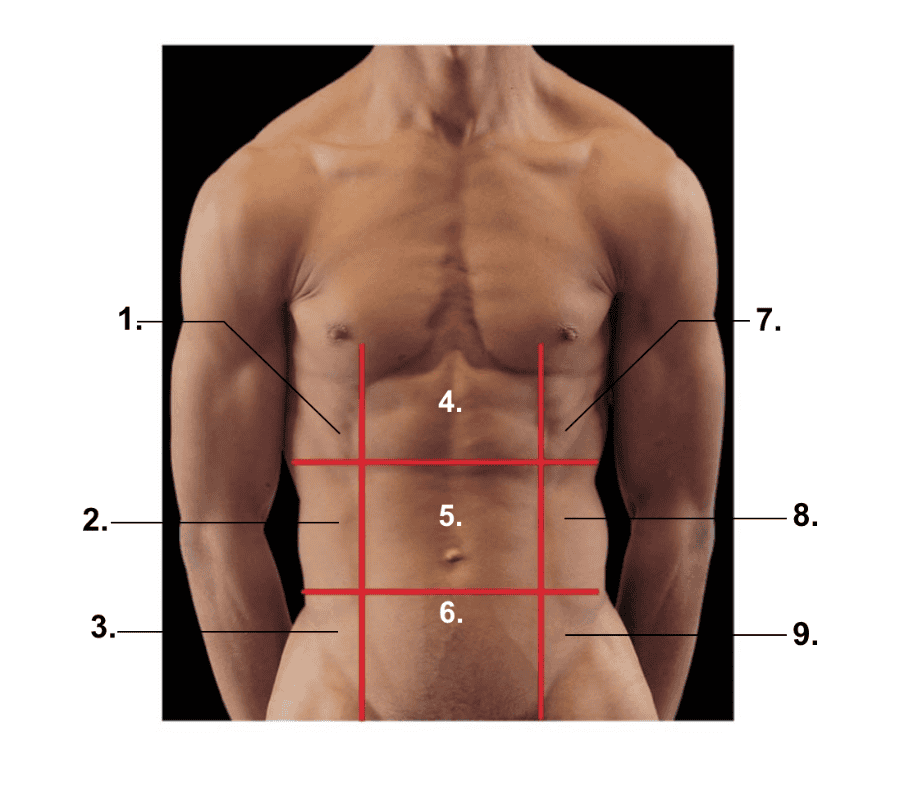

What is 1?

Right hypochondriac region

What is 2?

Right lumbar region

What is 3?

Right inguinal region

What is 4?

Epigastric region

What is 5?

Umbilical region

What is 6?

Hypogastric (pubic) region